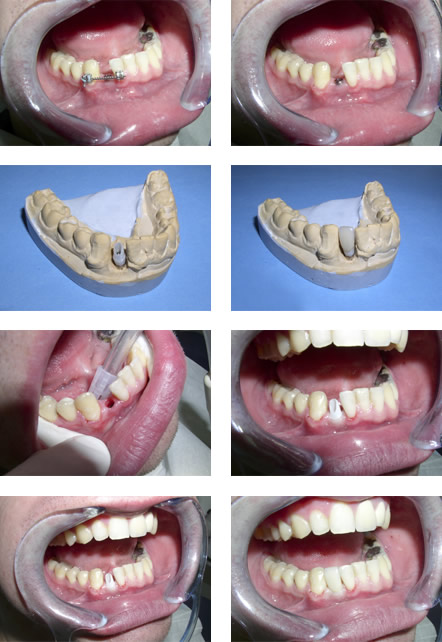

UGRADNJA IMPLATANATA | ||||||||||||||||||||||||||||||

| IZRADA BEZMETALNE NADOGRADNJE (PROCERA) |

| IZRADA BEZMETALNE KERAMIČKE KRUNICE |